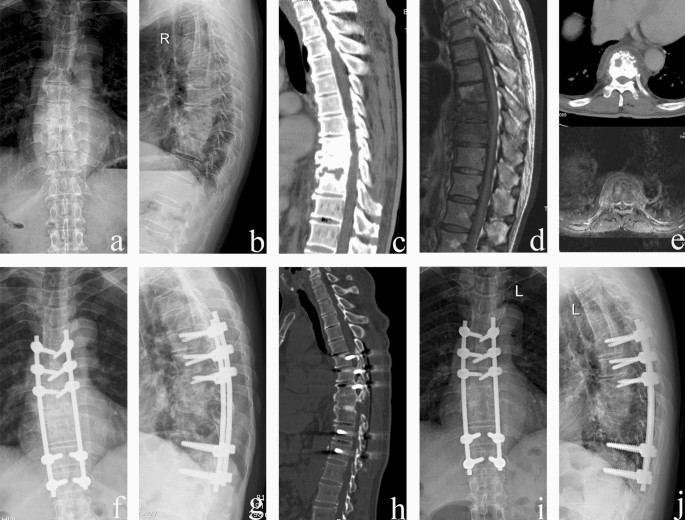

The average preoperative thoracic kyphosis angle was 34.4° ± 4.5°, which decreased to 22.0° ± 2.6° postoperatively. At the final follow-up, the mean deformity angle was 23.7° ± 2.1°, with only a 1.7° ± 1.1° correction loss (p < 0.05). Single-level debridement and interbody fusion were performed in 28 patients, and two-level procedures were completed in 14 patients. Spontaneous intervertebral bone fusion was achieved 10.6 ± 2.1 months after surgery (Table 2). No nonunion, pseudoarthrosis, loosening, or breakage were observed at the final follow-up (Figs. 3 and 4).

A 57-year-old male received a one-stage posterior transforaminal thoracic debridement, interbody fusion, and fixation. (a–e) Preoperative radiographs, CT, and MRI scans showed T8–T10 vertebral bone destruction, intervertebral space narrowing and paravertebral abscess formation. (f,g) Postoperative radiographs demonstrated that internal fixation was achieved in a good position. (h) CT showed that solid bone fusion was obtained at 12 months after surgery. (i,j) Radiographs displayed good internal fixation position and solid bone fusion, with no loss of correction after 66 months follow-up.